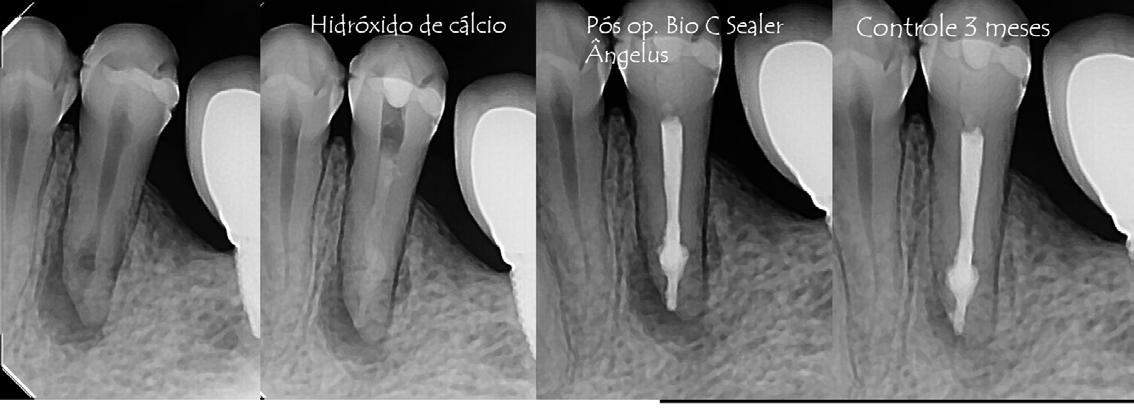

Prof. Dr. Warley Tavares

12/2017

Masculino

45 años

P. O. 3 meses

Reabsorción, Necrosis, Periodontitis Apical Crónica.

Instrumentación con NiTi, Hipoclorito de Sodio 2,5%, medicación con Hidróxido de Calcio por 10 días. Obturación con gutta percha y BIO-C® SEALER.

03/2018